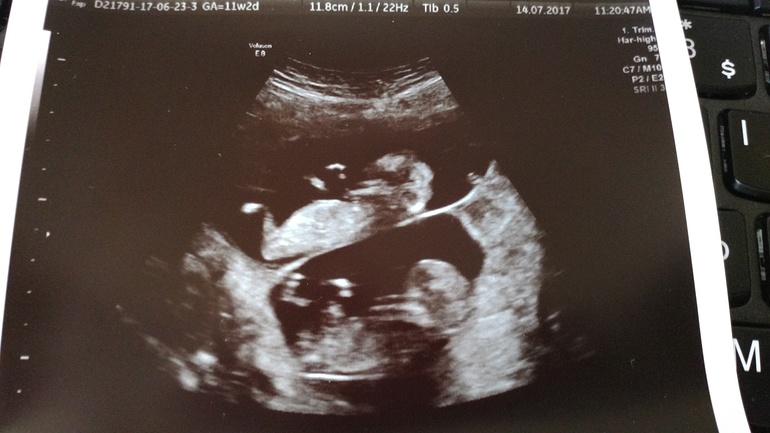

Первый скриннинг

Всё о нашей беременностиСегодня нам 12,4 недели и был первый скриннинг. 3 недели не видела малышей и так соскучилась за ними. Слёзы счастья сами непроизвольно текли по щекам. У малышей там была целая дискотека. Махали маме ручкой. У нас всё тьфу тьфу тьфу хорошо, а меня пока беспокоит только токсикоз

14.07.2017